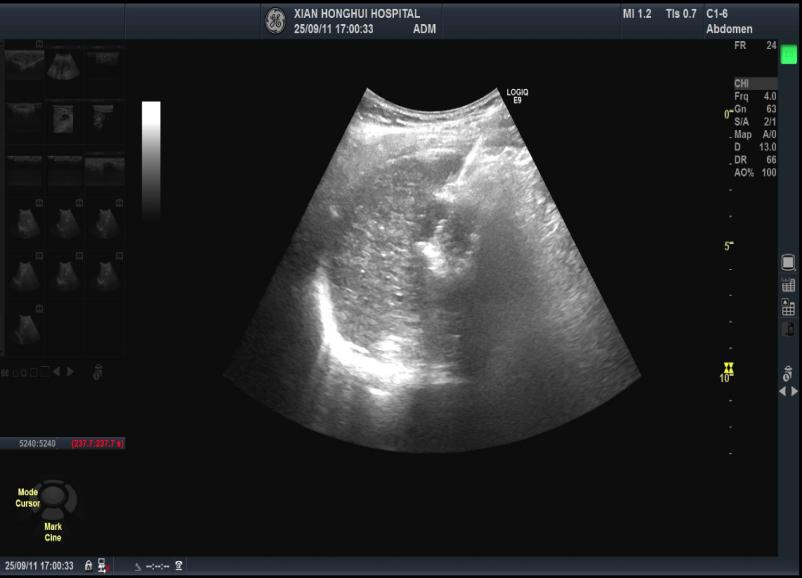

(超声引导下肝癌的射频消融)

在施育鹏副主任医师的带领下,团队联合超声医学科专家,精准实施“经皮经肝射频消融术”。手术在超声引导下进行,定位精准,操作顺利,全程仅用20分钟,成功完成肿瘤消融,患者术后恢复良好。

3. 穿刺消融: 在超声或CT的实时监控下,医生将消融针穿刺至肿瘤内,打开针尖,开始发射射频能量。整个过程需要几分钟到十几分钟不等。